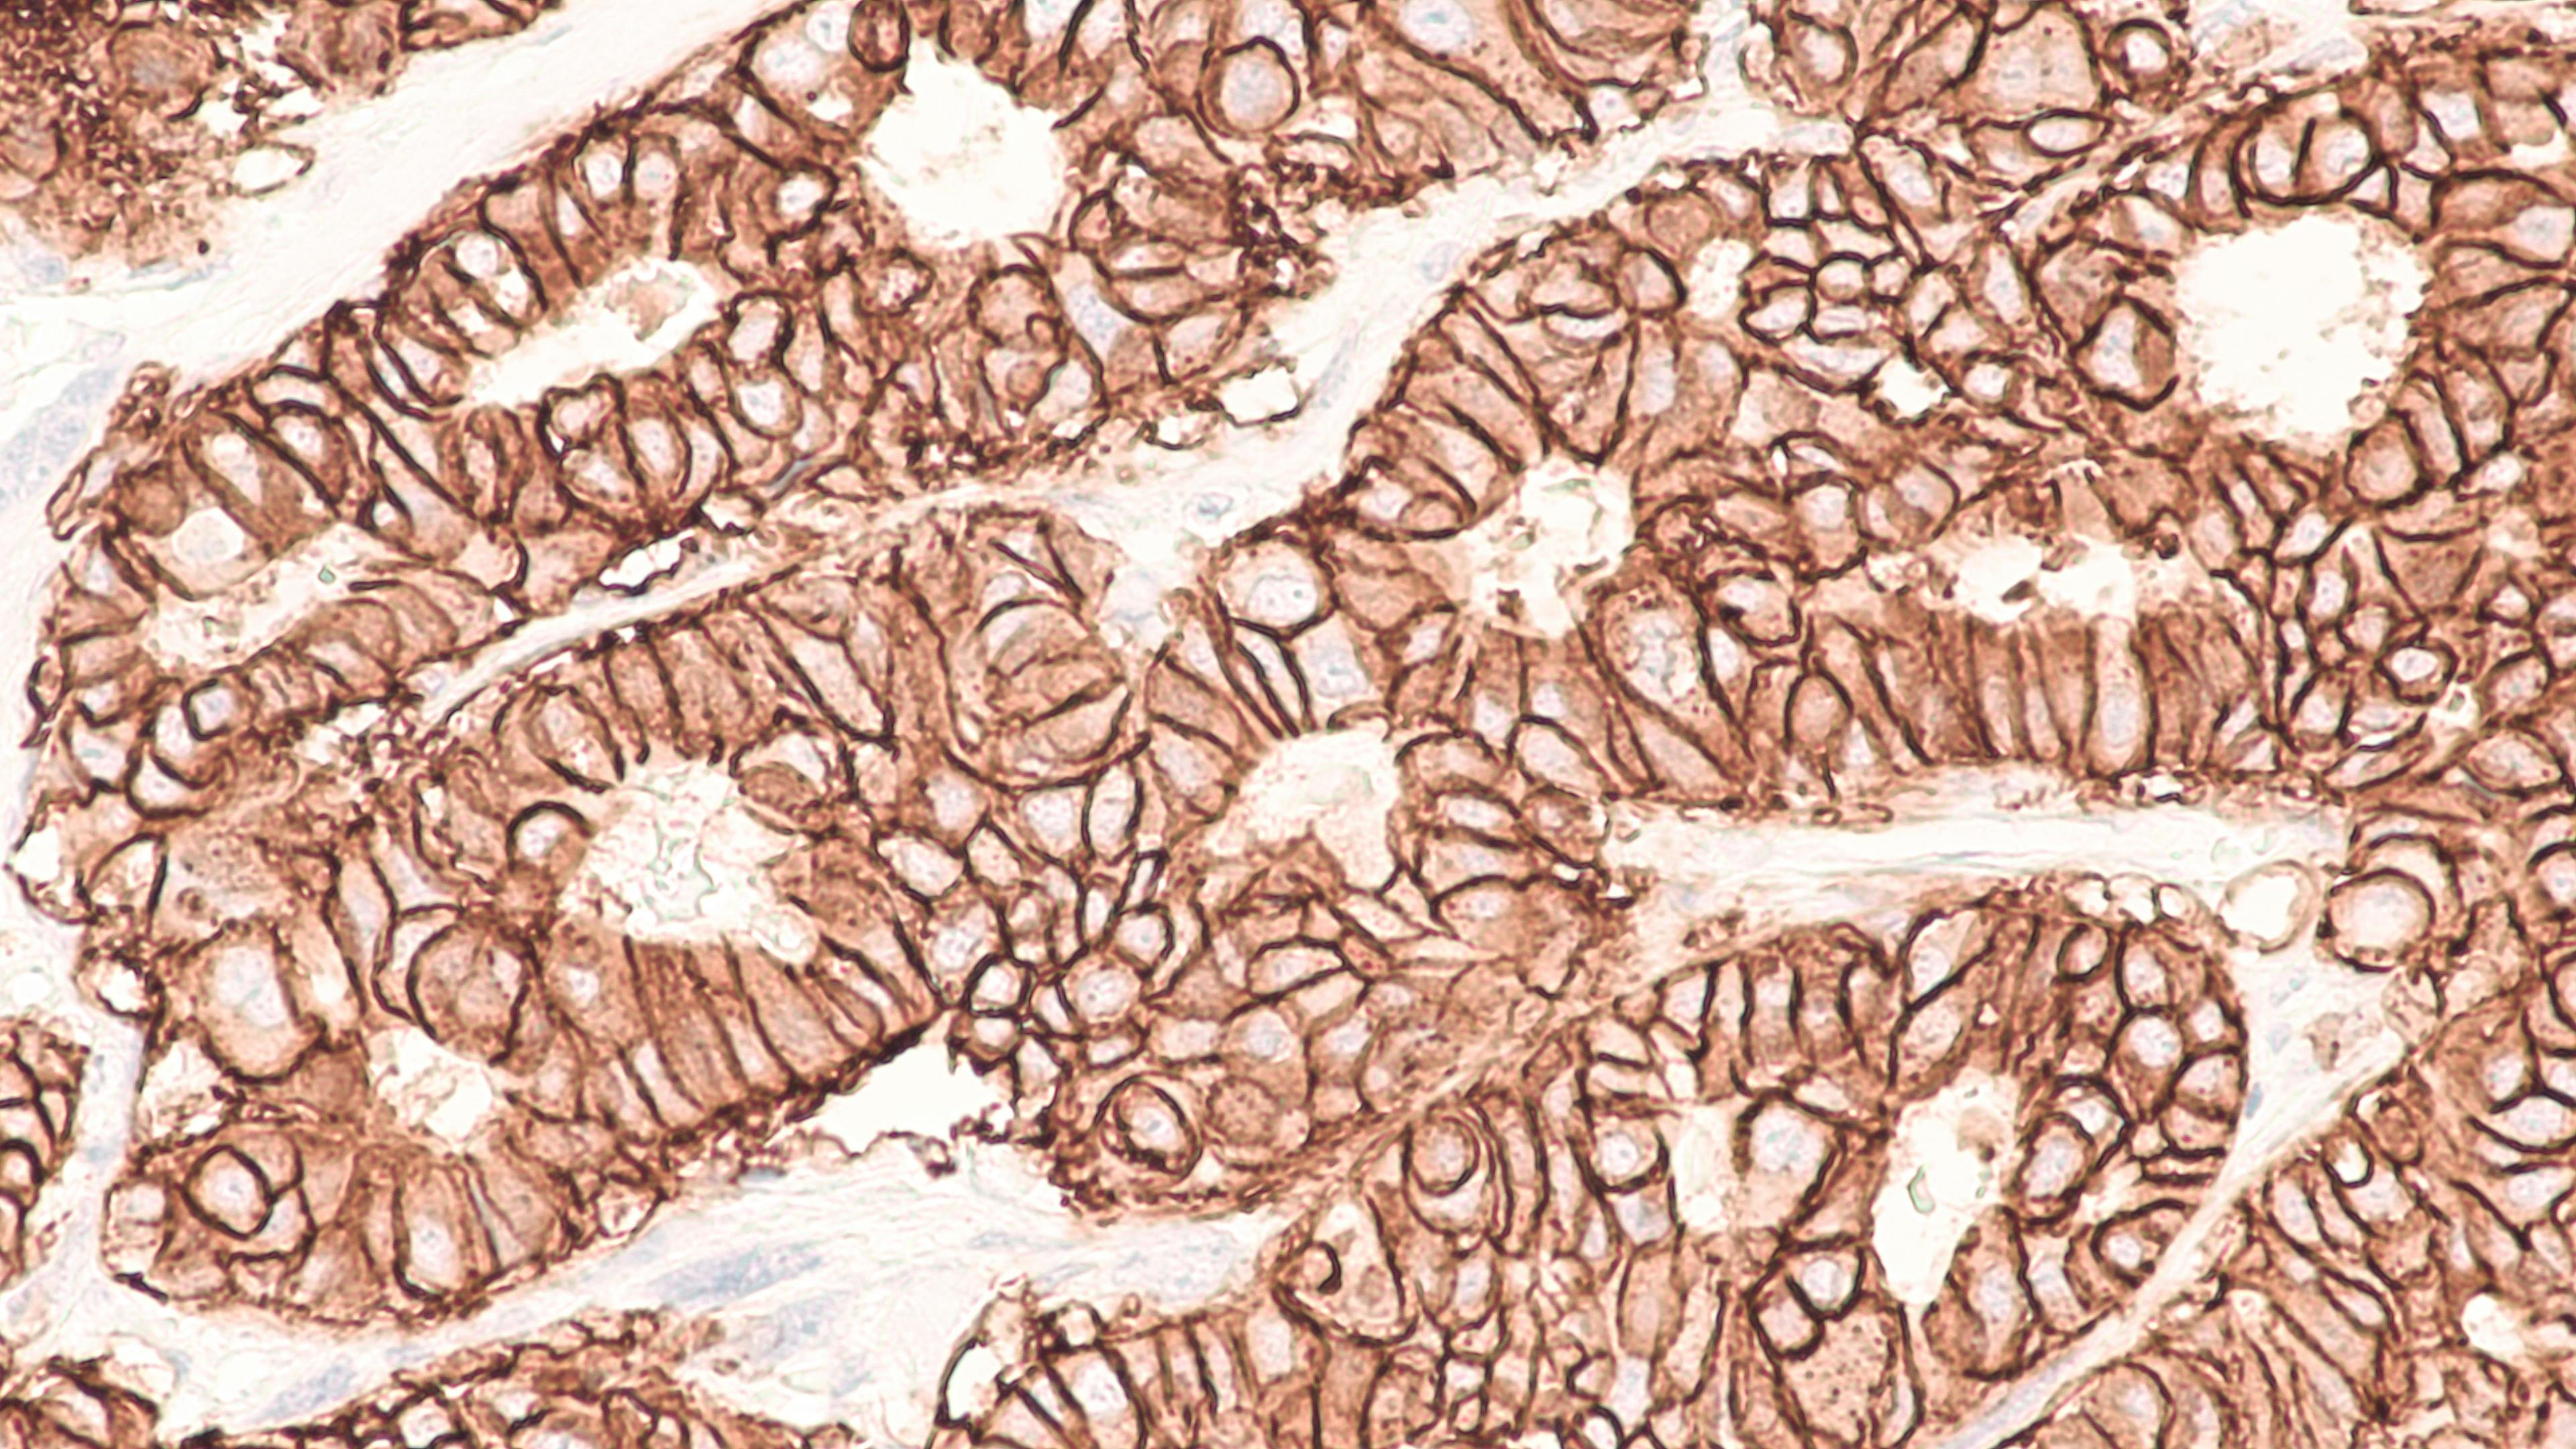

The program gives labs early access to OptraSCAN’s pay-per-slide model, enabling digital HER2 workflows without added staff or capital costs. By combining scanning and AI-powered quantitative interpretation (CPT 88361), labs can increase throughput, improve consistency, and scale testing more efficiently than manual HER2 scoring (CPT 88342).